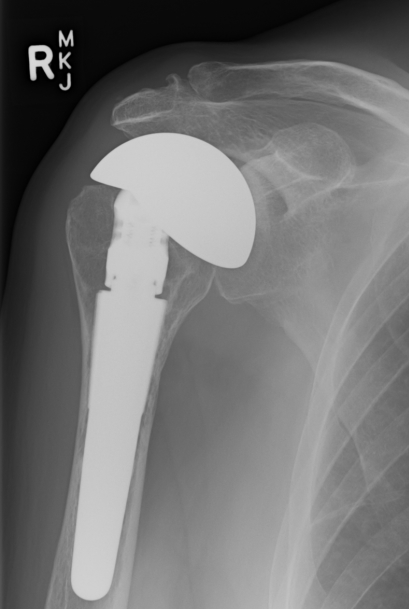

CTA Humeral Head / Extended Humeral Head Arthroplasty

Cuff Tear Arthropathy (CTA)

Extended humeral head prosthesis

- arc of surface > 180o

- allows articulation of lateral head with acromion

- increased articulation in abduction and external rotation

Indication

Young patient

Glenoid insufficiency

Revision from failed rTSA